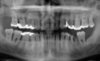

Cas 3: histoire radiographhique de maladie parodontale

Cas 4 : histoire radiographhique de maladie parodontale